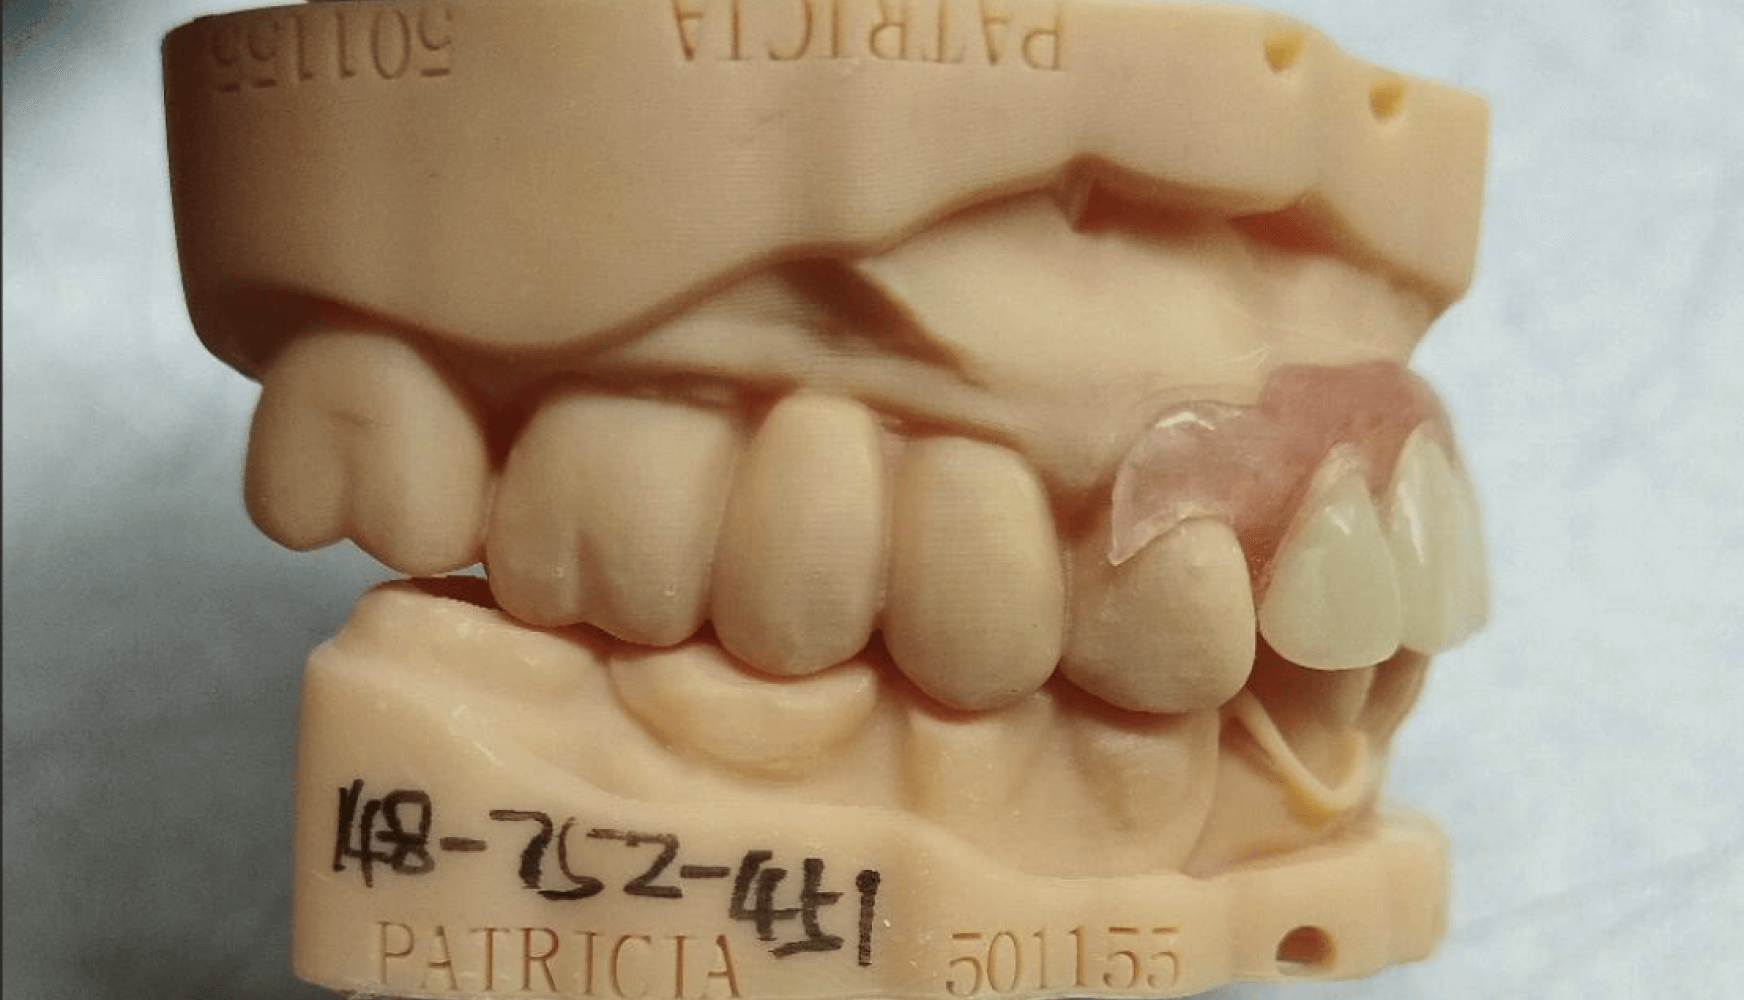

Figures 4a, 4b, 4c, 4d:

Figure 4a, 4b, 4c, 4d: The fabricated partial denture with its corresponding model. Both tissue shade and tooth shade met the patient’s expectations aesthetically and the overall clasping and fit did so as well.